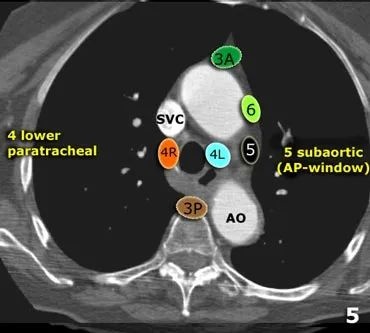

肺癌纵隔淋巴结分区

纵隔淋巴结分组图解

肺癌医生必备纵隔淋巴结分组图文解说

资源肺癌医生必备纵隔淋巴结分组图文解说再更新